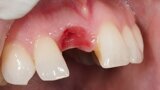

Figura 5. Hundimiento de la zona estética anterior inmediatamente después de la extracción del diente por la reabsorción de la pared vestibular.